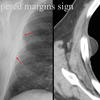

Tapered margins sign

Pleural or extrapleural origin